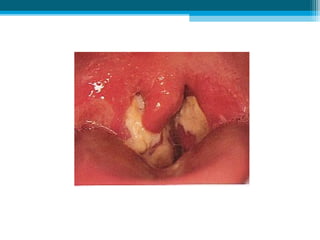

• Angine à fausses membranes :

▫ État : angine pseudo membraneuse, faciles à

enlever, confluentes, adhérentes sur l’amygdales et

la luette (pas toujours typique).